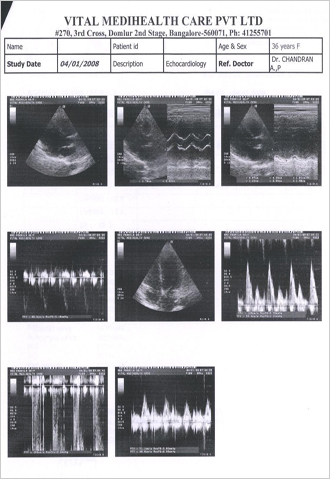

After a detailed discussion with patient following symptoms was taken for consideration of the and reprotorized using Radar 9 and screen shot of the window is given in FIG 2.

FIG 2:- Symptoms selected for the case